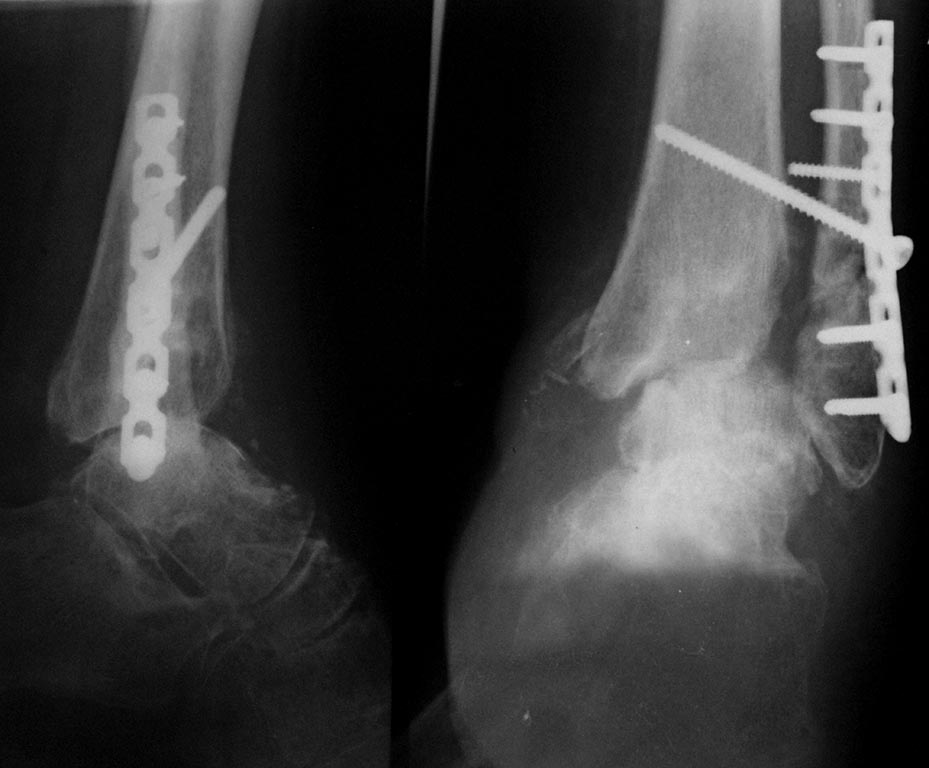

Больная,57лет, травма 2 года назад, переломы обеих лодыжек, выраженные

фликтены, длительный(около месяца) предопер. период. Неустраниимый

подвывих стопы кнаружи и кзади.

Открытая репозиция, синтез лодыжек, трансартикулярная фиксация спицами.

Удаление спиц через 8 недель с рецидивом подвывиха. Повторная операция,

трансартикулярная фиксация, вновь рецидив подвывиха. В июне 2013 года-

ревизия голеностопного сустава, удаление свободных фрагментов суставной

поверхности б/б кости, ревизия дельтовидной связки, устранение

транспозиции сухожилия по медиальной лодыжке, устранение подвывиха,

накостный синтез с установкой позиционного винта.

Сегодня такая картина. Жалобы на постоянные боли. Сгибание -разгибание

10 градусов. Планируем резекцию суставных, артродез с фиксацией

канюлированными винтами через пяточную кость.С последующей гипсовой

иммобилизацией на 3 месяца. Раздумываю над АВФ. Хотелось бы узнать

мнение о тактике, исходя из вашего опыта лечения таких больных. Спасибо.